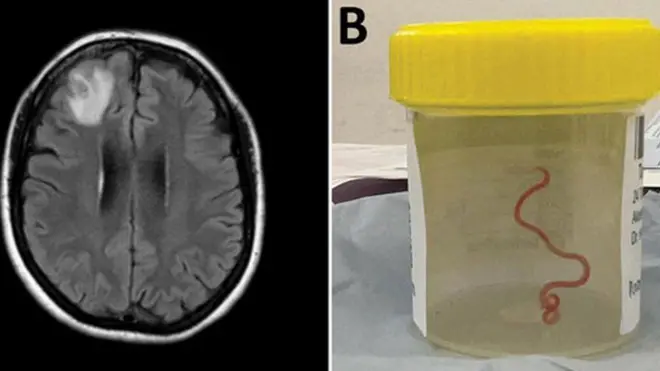

کشف کرم زنده در مغز

دانشمندان برای نخستین بار در تاریخ یک کرم زنده ۸ سانتیمتری را از مغز یک زن استرالیایی خارج کردند.

این «سازه نخمانند» را سال گذشته با جراحی در کانبرا از لوب پیشانی آسیبدیده بیمار خارج کردند، اما گزارش آن امسال منتشر شد.

هاری پریا باندی، پزشک جراح، گفت «قطعا آن چیزی که انتظار داشتیم نبود. همه را تکان داد.»

این زن ۶۴ ساله ماهها بود که از نشانههایی مانند شکمدرد، سرفه و عرق شبانه که در ادامه به فراموشی و افسردگی منجر شد رنج میبرد.

او را در اواخر ژانویه ۲۰۲۱ در بیمارستان بستری کردند و تصویربرداریها حاکی از وجود «یک ضایعه غیرعادی داخل لوب پیشانی راست مغز» بود.

اما دلیل وضعیت او تنها با چاقوی جراحی دکتر باندی و نمونهبرداری در ژوئن ۲۰۲۲ مشخص شد.

به گفته پزشکان این انگل قرمزرنگ شاید به مدت دو ماه داشته در مغز او زندگی میکرده است.

بنا بر گزارش پژوهشگران در ژورنال بیماریهای عفونی نوظهور گمان میرود که این مورد نخستین نمونه از ورود و رشد لارو در مغز انسان باشد. آنها هشدار میدهند که این اتفاق خطر انتقال بیماری و عفونت از حیوانات به انسان را برجسته میکند.